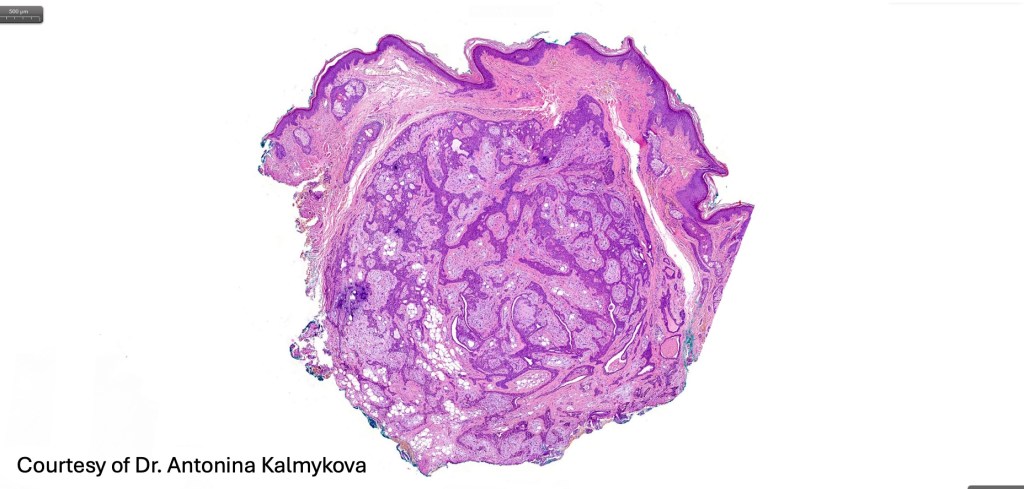

•Well circumscribed unencapsulated, nodular/multinodular silhouette composed of an admixture of epithelial & mesenchymal elements

•Often intensely basophilic due to mucinous deposits

•Mixed epithelial component including nests & cords of epithelium with abundant, eosinophilic cytoplasm & small vesicular nuclei

•Clear cell change

•Glandular differentiation sometimes showing apocrine differentiation

•Myoepithelial layer in glandular foci

•Mucinous metaplasia

•Ductal differentiation

•Cribriform/retiform appearance occasionally evident

•Mitoses very rare or absent

•No necrosis